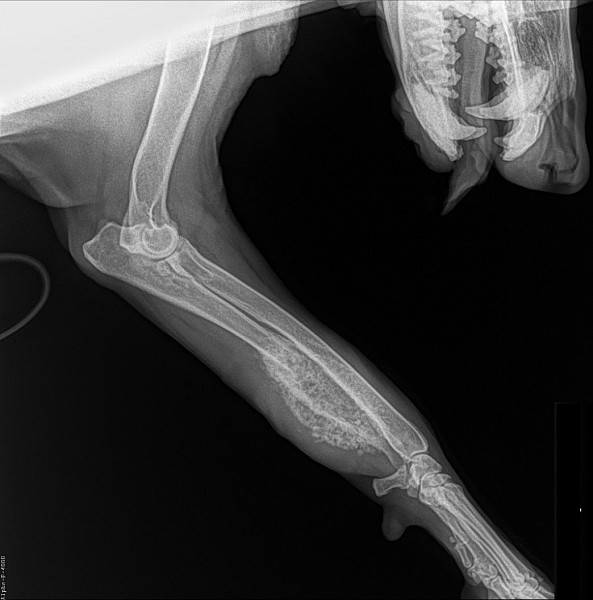

Рентгеновские снимки перелома лапы у кота: диагностика и лечение